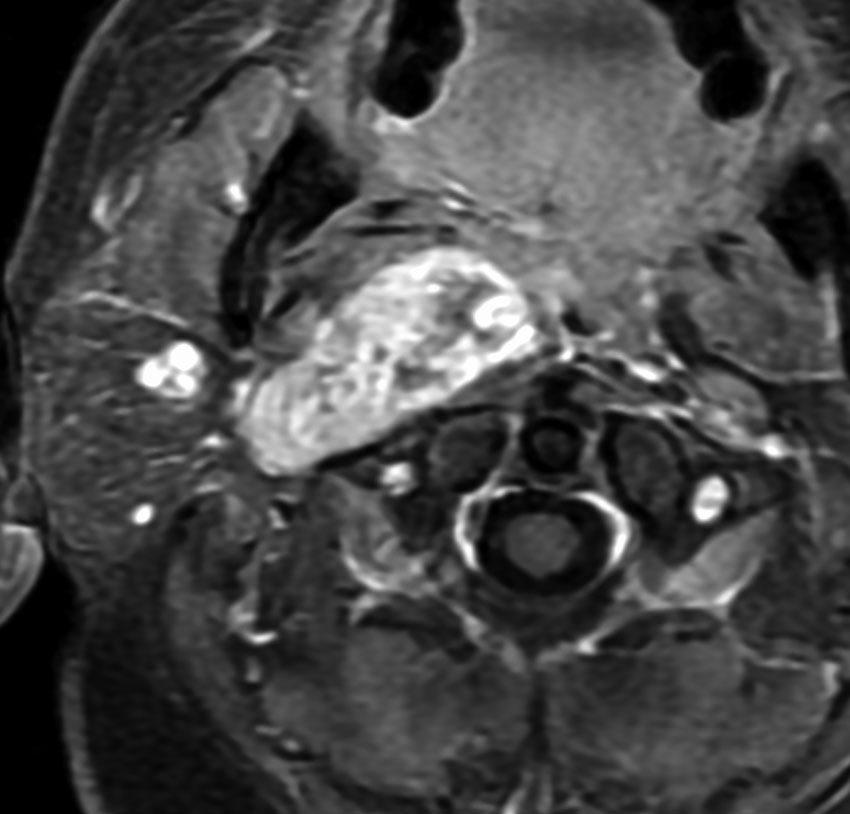

症例:気道狭窄を呈したもの:副咽頭間隙腫瘍 parapharyngeal tumor

頸静脈孔にも腫瘍があり頸部へ伸展した迷走神経鞘腫です。咳が出る,右下にして寝ると痰が詰まる,咽せるという症状で発症しました。摘出すると嚥下障害が出る可能性があるので,9年間経過観察しました。徐々に増大して,正中方向へ伸展して気道狭窄を生じました。睡眠時無呼吸,痰が詰まって苦しくなって夜中に目覚めてしまうという症状になりました。

内部から核出 enucleationしました。腫瘍周辺に迷走神経組織があるので,中心から内部の腫瘍だけを摘出減荷する方法です。左術前,右術後。